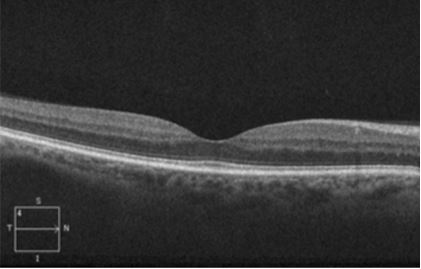

Ocular Coherence Tomography (OCT) scan of eye showing normal anatomy of the photoreceptor segments of retina. Image © E. Mitchel Opremcak, M.D., www.theretinagroup.com